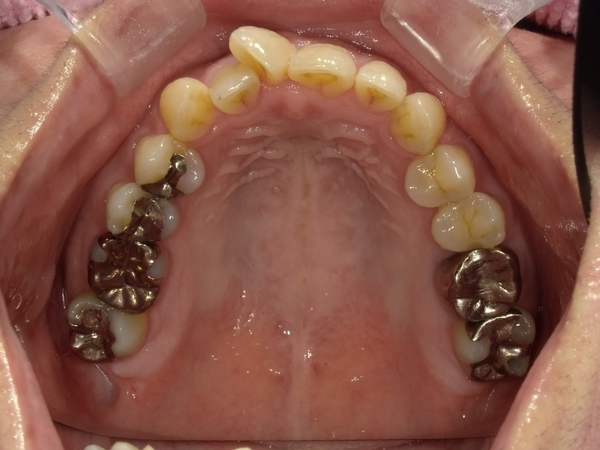

ガタガタとした歯並びや八重歯(叢生)CASE71